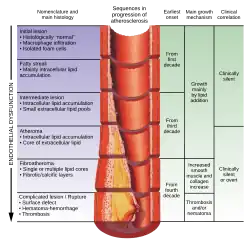

Atherogenesis is the developmental process of atheromatous plaques. It is characterized by a remodeling of arteries leading to subendothelial accumulation of fatty substances called plaques. The buildup of an atheromatous plaque is a slow process, developed over several years through a complex series of cellular events occurring within the arterial wall and in response to several local vascular circulating factors. One recent hypothesis suggests that, for unknown reasons, leukocytes, such as monocytes or basophils, begin to attack the endothelium of the artery lumen in cardiac muscle. The ensuing inflammation leads to the formation of atheromatous plaques in the arterial tunica intima, a region of the vessel wall located between the endothelium and the tunica media. Chronic inflammation within the arterial wall, driven by immune cells like macrophages, accelerates atherosclerotic plaque instability by promoting collagen breakdown and thinning the fibrous cap, which increases the likelihood of rupture and thrombosis.[64] The bulk of these lesions is made of excess fat, collagen, and elastin. At first, as the plaques grow, only wall thickening occurs without narrowing. Stenosis is a late event, which may never happen and is often the result of repeated plaque rupture and healing responses, not just the atherosclerotic process.[65] Autopsy studies have shown that the prevalence of coronary artery atherosclerosis in males from the United States, with an average age of 22.1 years, who died in war, ranges from 45% to 77.3%.[66]

Although arteries are not typically studied microscopically, two plaque types can be distinguished:[72]

- The fibro-lipid (fibro-fatty) plaque is characterized by an accumulation of lipid-laden cells underneath the intima of the arteries, typically without narrowing the lumen due to compensatory expansion of the bounding muscular layer of the artery wall. Beneath the endothelium, there is a "fibrous cap" covering the atheromatous "core" of the plaque. The core consists of lipid-laden cells (macrophages and smooth muscle cells) with elevated tissue cholesterol and cholesterol ester content, fibrin, proteoglycans, collagen, elastin, and cellular debris. In advanced plaques, the central core of the plaque usually contains extracellular cholesterol deposits (released from dead cells), which form areas of cholesterol crystals with empty, needle-like clefts. At the periphery of the plaque are younger "foamy" cells and capillaries. These plaques usually produce the most damage to the individual when they rupture. Cholesterol crystals may also play a role.[73]

- The fibrous plaque is also localized under the intima, within the arterial wall, resulting in thickening and expansion of the wall and, sometimes, spotty localized narrowing of the lumen with some atrophy of the muscular layer. The fibrous plaque contains collagen fibers (eosinophilic), precipitates of calcium (hematoxylinophilic), and, rarely, lipid-laden cells.

- Calcification at the outer base of older or more advanced lesions. Atherosclerotic lesions, or atherosclerotic plaques, are separated into two broad categories: Stable and unstable (also called vulnerable).[79] The pathobiology of atherosclerotic lesions is very complicated, but generally, stable atherosclerotic plaques, which tend to be asymptomatic, are rich in extracellular matrix and smooth muscle cells. On the other hand, unstable plaques are rich in macrophages and foam cells, and the extracellular matrix separating the lesion from the arterial lumen (also known as the fibrous cap) is usually weak and prone to rupture.[80] Ruptures of the fibrous cap expose thrombogenic material, such as collagen,[81] to the circulation and eventually induce thrombus formation in the lumen. Upon formation, intraluminal thrombi can occlude arteries outright (e.g., coronary occlusion), but more often they detach, move into the circulation, and eventually occlude smaller downstream branches, causing thromboembolism.